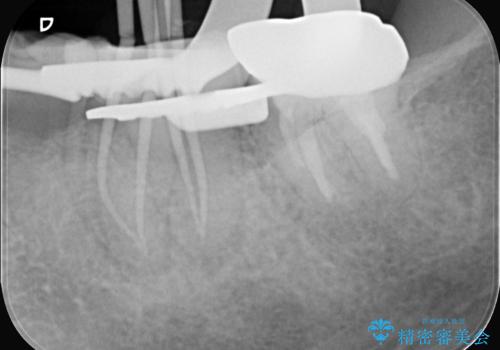

大きい虫歯 根管治療〜オールセラミッククラウン

- 歯が欠けたことを主訴に来院されました。

再根管治療後、歯周外科を行い、オールセラミッククラウンにて修復処置を行っております。

根管治療を行った大臼歯は速やかに被せ物の治療を行うことが必要です。